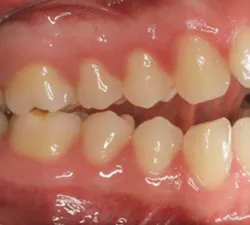

Review the example below.

Q: According to Angle’s classifications of occlusion, the patient has:A. Normal occlusion

B. Class I malocclusion

C. Class II malocclusion

D. Class III malocclusion

Answer: C. Class II malocclusion

To solve the question, first identify the mesiobuccal cusp of the maxillary first molar and see if it fits in the mesiobuccal groove of the mandibular first molar. In this case, the mesiobuccal cusp of the maxillary first molar is “anterior” to the groove of the mandibular first molar. Therefore, we can conclude that the patient has Class II malocclusion. Class II malocclusion can be further divided into Division 1 or Division 2, but this cannot be determined since the anterior teeth are not presented in the case.